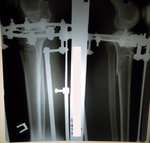

Исходник - 35 лет.

Укорочение правой ноги - 2 см.

Левая голень более деформирована.

Дата операции 22.03.2016г.

Дата снятия аппаратов 22.06.2016г.

Срок лечения 90 дней.

Диагноз: Укорочение правой ноги - 2 см.